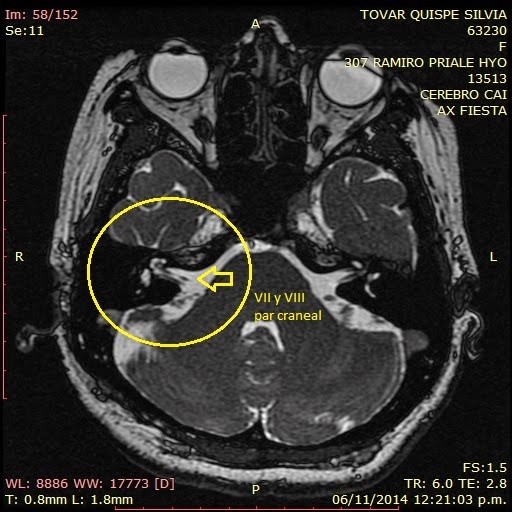

Que Se Ve En Una Resonancia De Oído, VIDEO DE RMI DE OIDOS, 72.97 MB, 53:08, 2,496, Horacio Tenuto, 2021-05-08T05:05:53.000000Z, 3, 17.casos clinicos hipoacusias perceptivas, es.slideshare.net, 728 x 546, jpeg, WebUna Resonancia de Oído es un estudio correspondiente a la Resonancia Magnética, en el cual se obtienen imágenes de alta definición anatómica del oído interno,. WebLas indicaciones de la Rm de casi, aunque no se limitan a estas, son las siguientes: Procesos expansivos relacionados con los nervios craneales faciales y acústico, como el., 20, que-se-ve-en-una-resonancia-de-oido, Novedades y Muebles WebUna Resonancia de Oído es un estudio correspondiente a la Resonancia Magnética, en el cual se obtienen imágenes de alta definición anatómica del oído interno,. WebLas indicaciones de la Rm de casi, aunque no se limitan a estas, son las siguientes: Procesos expansivos relacionados con los nervios craneales faciales y acústico, como el.

WebConsiste en la obtención de imágenes de alta definición anatómica del oído interno mediante el empleo de un campo electromagnético y ondas de radio (con un emisor y un. WebUna angiografía por resonancia magnética (ARM) es una forma de imagen por resonancia magnética que crea imágenes tridimensionales de los vasos sanguíneos. Resultados. WebLa resonancia magnética se considera una de las formas más seguras y efectivas de detectar diversas patologías del ojo, examinando cuidadosamente las. WebLa resonancia magnética sirve para detectar tumores, pero en los años 90 se descubrió que podrían servir para obtener otras informaciones. Cómo funciona la. WebEl oído externo (OE) es accesible al examen directo. En la mayor parte de las enfermedades, la historia clínica y la otoscopia son suficientes para su diagnóstico y. WebLa resonancia magnética cerebral (RM cerebral) es uno de los estudios más solicitados de imagenología médica. Permite a los médicos enfocarse en varias partes del encéfalo y. WebEl profesional que solicita un estudio de imágenes de Resonancia Magnética indicará siempre la región que debe ser evaluada. El motivo del estudio,. WebAl cabo de cuatro horas, tiempo en el que se calcula que el gadolinio ha difundido al oído interno, se le realiza al paciente una resonancia magnética de 3.